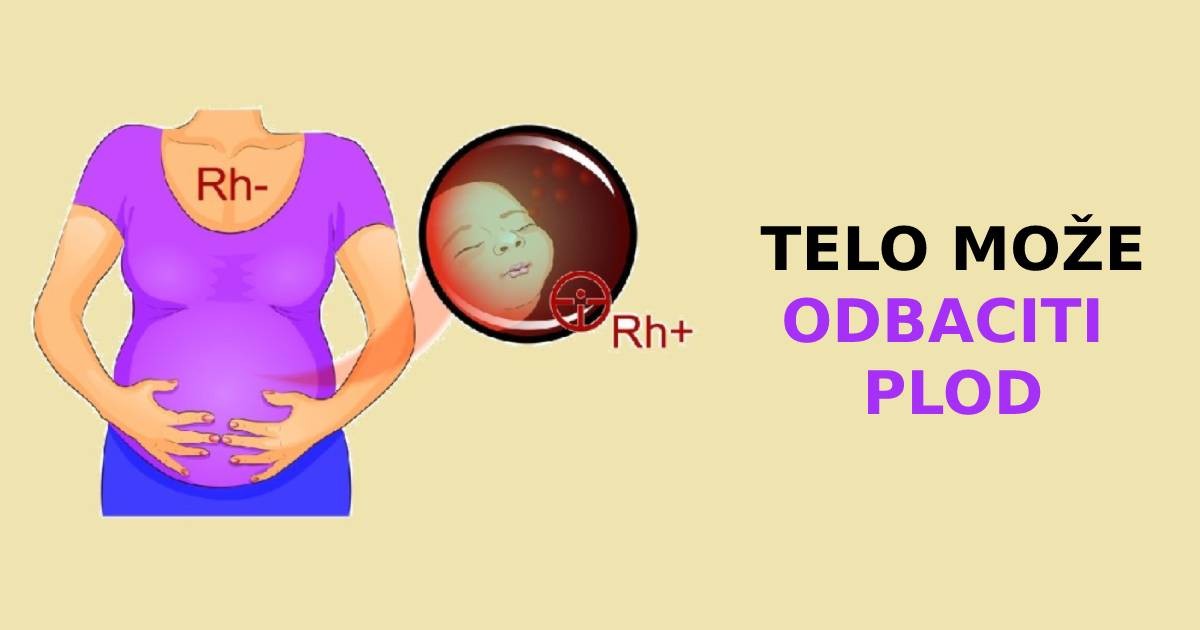

Bez obzira na vašu krvnu grupu, postoji još jedan veoma važan pokazatelj koji ne biste trebali zaboraviti. Ovo je Rh faktor krvi. Ako na površini vaših crvenih krvnih zrnaca postoji protein antigena, onda je vaša krv Rh-pozitivna. Ali ima oko 15% ljudi koji nemaju ovaj antigen i oni, shodno tome, imaju negativan Rh faktor. Upravo ovo prisustvo / odsustvo proteina zanima mnoge naučnike koji su naučili zanimljive stvari tokom svog istraživanja.